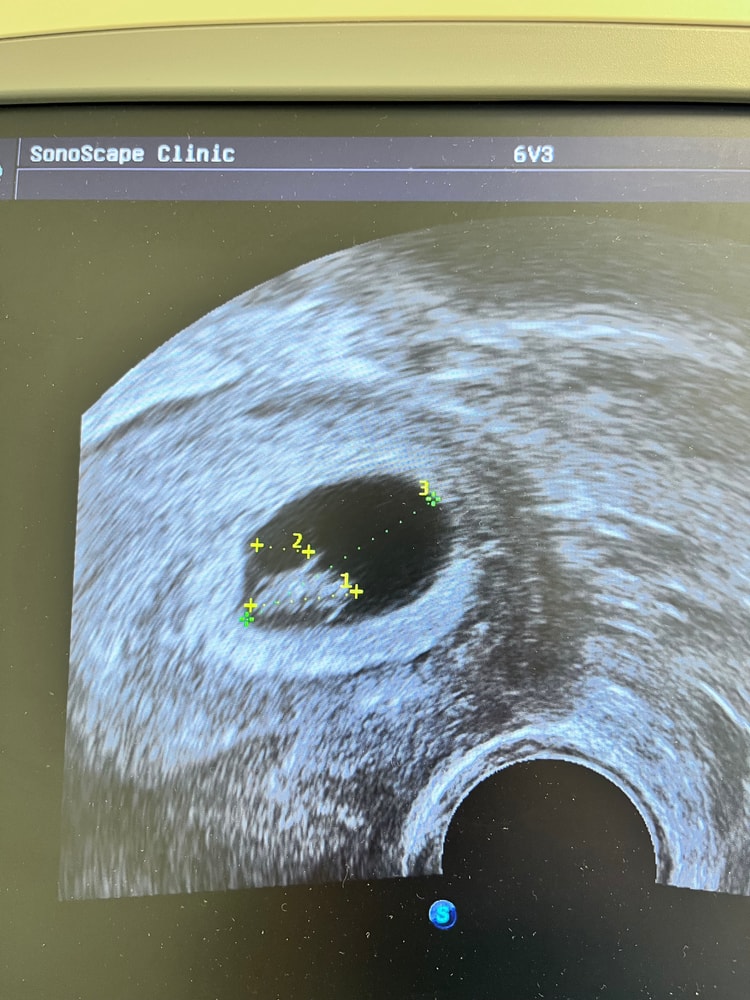

Сегодня была на узи у моей ре. Малыш 10,8 мм, сб +. Срок по месячным 7,6. Репродуктолог отменила прогинову, эстрожель. Расписала схему приема с последующим снижением утрожестана и дюфастона и отпустила в свободное плавание 🐠. Вставать на учет в жк по месту жительства и тд. Очень тепло с ней поговорили, сказала будет ждать за остальными криошками 😅. Записалась на узи на 30.12 в мою клинику, но к другому врачу. Девочки, неужели новогоднее чудо случилось?! 🙏